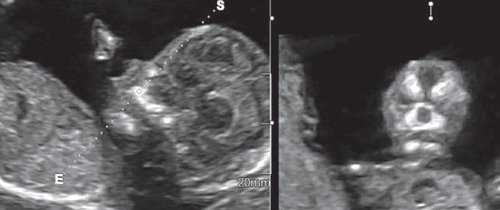

Революцией в пренатальной ультразвуковой диагностике явилось появление объемной эхографии, которая, обладая такими качествами, как неинвазивность, безопасность и возможность многократного применения у одной пациентки, имеет высокую информативность в исследовании анатомии плода и изучении его фенотипа. При применении различных режимов объемной эхографии абсолютно очевидно их преимущество по сравнению с обычным сканированием. Детально можно изучить лицо плода (рис. 1-4) в различные сроки беременности, начиная со сроков первого пренатального скрининга в 11-14 нед, конечности плода, причем не только их наличие и положение (рис. 5, 6), но и состояние и количество пальцев (рис. 7-9) как на руках, так и на ногах. Также можно изучить позвонки плода (рис. 10), состояние твердого нёба (рис. 11, 12), строение наружного уха (ушной раковины) (рис. 13), состояние основных швов черепа и родничков, исключая их преждевременное закрытие при кранисиностозах (рис. 14, 15).

Методика базируется на изучении коронарного скана лица плода, так называемого ретроназального треугольника, при котором визуализируется верхняя и нижняя челюсть. Техника получения этого скана чрезвычайно проста и может быть рекомендована для скринингового исследования в 11-14 нед беременности. Эта методика позволяет оценить нижнюю челюсть плода без применения трудоемких оценок, и не сопряжена с математически сложными расчетами коэффициентов, также она существенно не увеличивает время осмотра. Коронарный скан можно оценивать как в режиме 2D, так и в режиме объемной эховизуализации 3D. Методика оценки коронарного скана лица плода в I триместре беременности показана на рисунке 6.

Обе ветви нижней челюсти при сроке 11-14 нед беременности выглядят гиперэхогенными, а в месте слияния имеют характерный гипоэхогенный промежуток, ультразвуковой "разрыв". Этот признак визуализируется при нормальном развитии нижней челюсти (mandibular "gap").

Такие особенности ультразвуковой анатомии связаны с этапами эмбрионального развития костей нижней челюсти, ветви которой начинают развиваться из первой жаберной дуги с 7-й недели эмбрионального развития (рис. 7), и, постепенно приближаясь друг к другу к концу I триместра (на 14-й неделе беременности), образуют синостоз в области подбородка.

Размер этого промежутка уменьшается с увеличением срока беременности. Нижнечелюстной промежуток здорового плода представлен на рисунке 8.